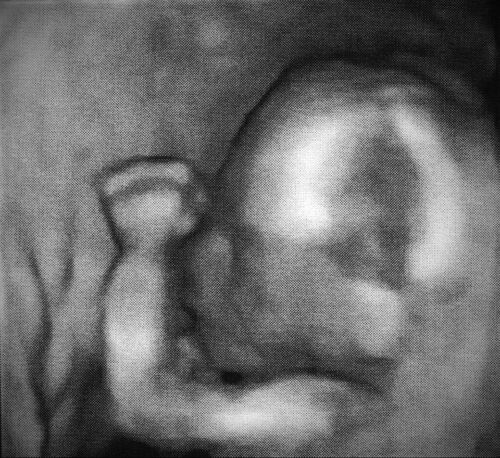

Kindsmord beginnt bereits dann, wenn das im Mutterleib gezeugte und heranwachsende Kind getötet wird. Kindsmord ist immer das Ergebnis menschlicher Sünde und zeigt das ganze Unheil in dieser Welt. Das Böse ist heute dort real und grausam, wo Kindsmord – wie in diesen Tagen proklamiert – zum Menschenrecht erklärt wird.

Damals waren es Hethiter, Amoriter, Kanaaniter, Perisiter, Hiwiter und Jebusiter, die Kinderopfer praktizierten, Gottes Gebote mit Füßen traten (5.Mose 7,1-2) und über die letztlich Gottes Strafgericht hereinbrach. Heute ist es die Europäische Union samt den Mitgliedsstaaten, die Abtreibung ungeborenen Lebens fördern, Kinder auf bestialische Weise zerstückeln und wie Abfall in Brennöfen entsorgen lassen.